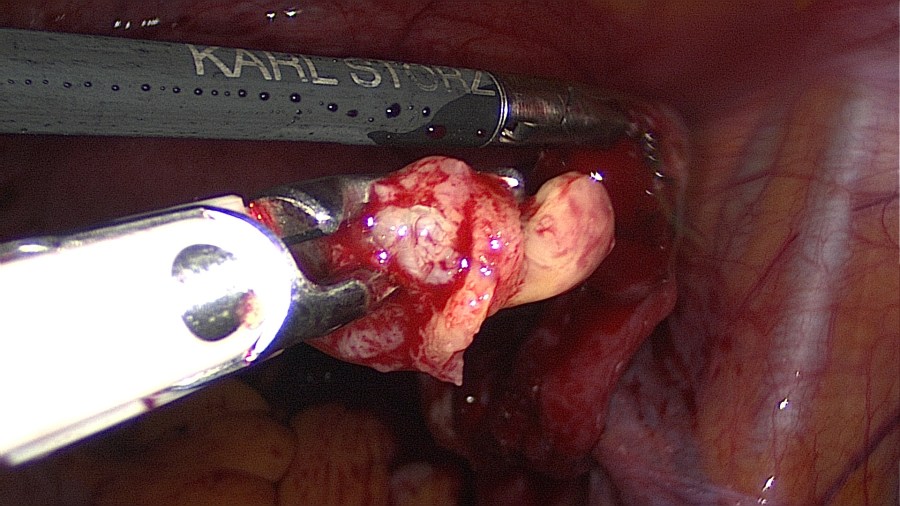

The patient came to us for removal. In our work-up we asked for a preoperative low-dose abdomen CT, which verified intraperitoneal lie of the IUD and excluded bowel involvement.

Interestingly, the patient had experienced the desired amenorrhea for almost 5 years, despite the fact that the IUD was lying inside the greater omentum and not inside the uterus.